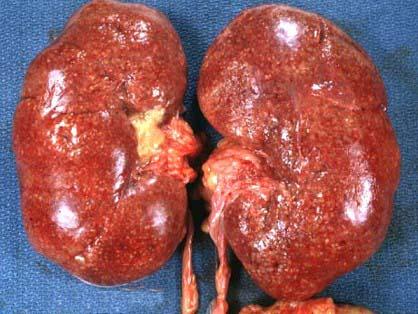

问题 死者,女性,28岁。因败血症死亡。发病初期曾有持续发热、腰痛、尿频、尿急、脓尿等症状。尸检见双肾肿大,包膜紧张,肾盂肾盏黏膜充血、水肿、表面有脓性分泌物,并可见小脓肿(如图),镜检如图所示,正确诊断为 ( )

选项 A.肾结核 B.慢性肾小球肾炎 C.急性肾盂肾炎 D.高血压性肾病 E.以上都不正确

答案 C